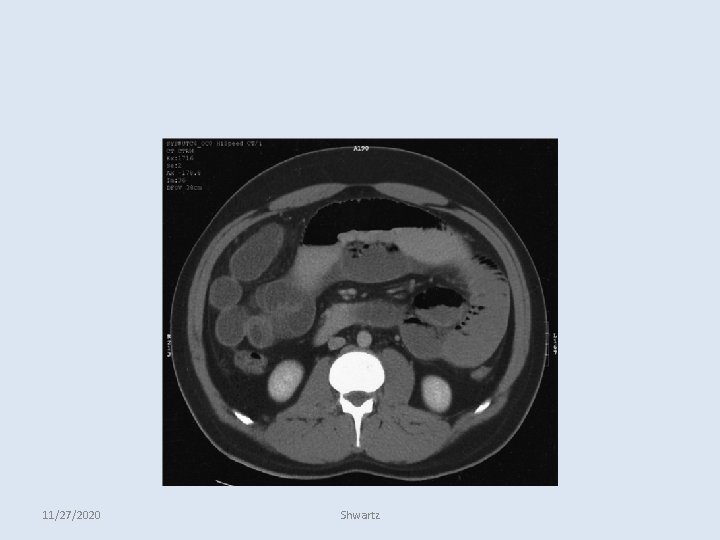

SMALL-BOWEL OBSTRUCTION • CT Abdomen: • Findings include: – A discrete transition zone with dilation of bowel proximally, decompression of bowel distally – intraluminal contrast that does not pass beyond the transition zone – Colon containing little gas or fluid. – Strangulation is suggested by: • Thickening of the bowel wall • Pneumatosis intestinalis (air in the bowel wall) • Portal venous gas • Mesenteric haziness • Poor uptake of intravenous contrast into the wall of the affected bowel. – CT scanning also offers a global evaluation of the abdomen and may 11/27/2020 therefore reveal the etiology of obstruction. Shwartz

SMALL-BOWEL OBSTRUCTION 11/27/2020 Shwartz